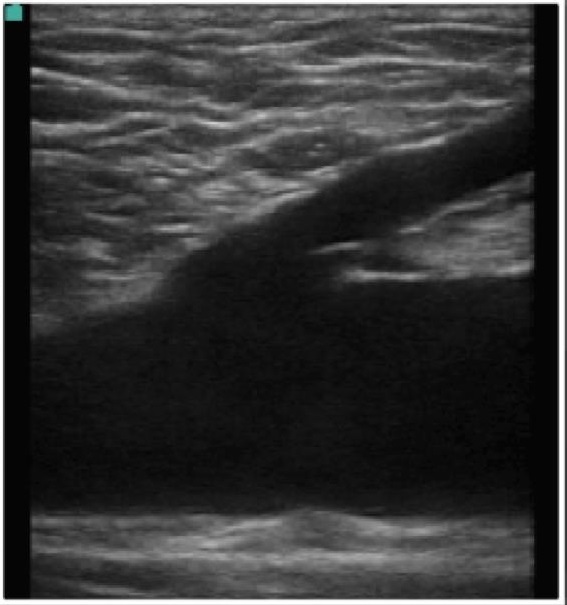

Bild 2: Gefäß, lange Venen